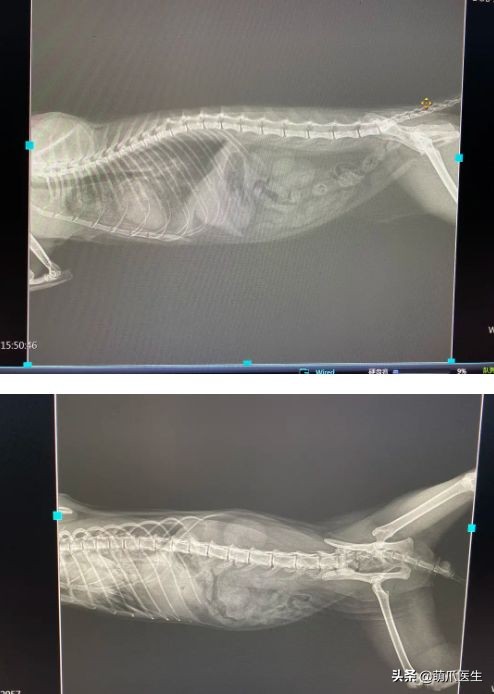

最后我们看一下X光片

go猫粮吃了拉黄水,go猫粮吃了会黑下巴吗

腹腔未见明显异常,而胸腔里肺部有一些渗出心脏稍圆润偏大

前面说到,十一的生化检查结果显示有心肌损伤的可能性,并且X光片发现肺部有水肿或者渗出

而肺水肿会导致呼吸困难,每分钟呼吸次数超过50次。并出现严重的腹式呼吸

主人说猫咪下午腹部出现抽搐,可能是呼吸困难导致的。